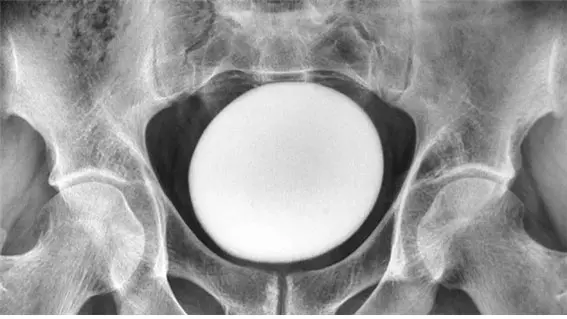

의료진이 복부를 진찰한 결과, 차골 위쪽에서 크고 매끄러우며 단단한 덩어리가 만져졌다. 이 덩어리는 골반이나 복벽에 붙어있지 않았으며, 초음파 검사 결과 지름 약 11cm의 달걀 모양 물체로 확인됐다.

의료진은 결석이 요로를 막거나 압박하고 있지 않는지 확인한 뒤 방광결석제거술로 결석을 제거했다. 제거된 결석은 무게 826g, 길이 약 13cm, 너비 약 10cm, 높이 약 8cm에 달했다. 결석이 워낙 커 방광 뒤쪽까지 절개 부위를 확장해야 했다. 남성은 수술 후 회복 과정에서 배뇨를 돕기 위해 7일간 도뇨관을 착용했다.